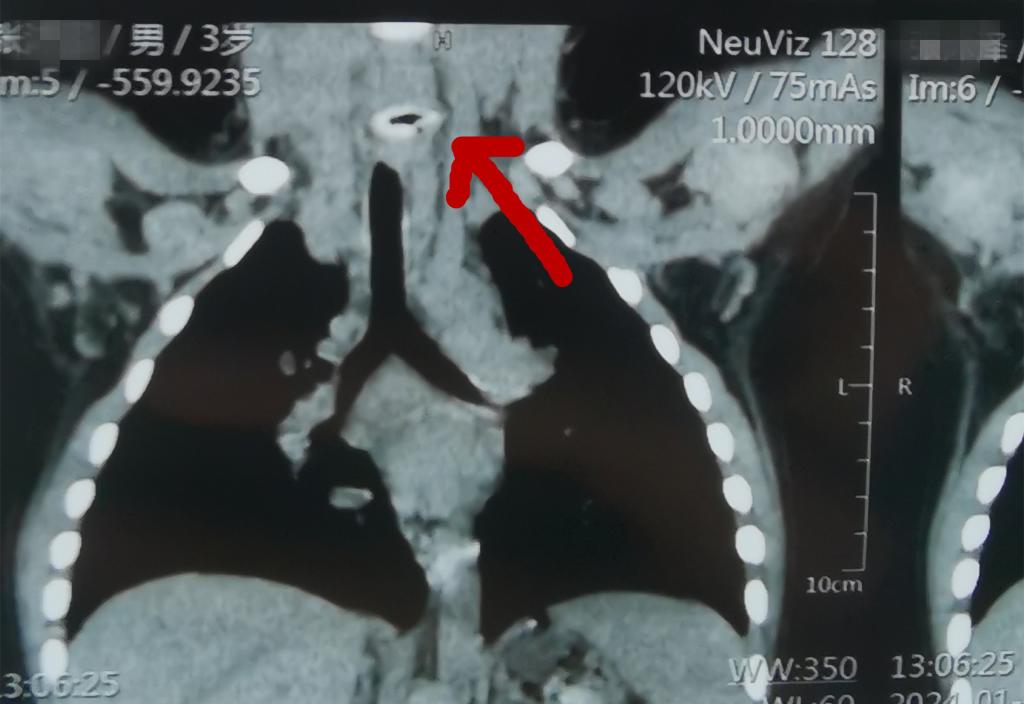

原来,哲哲在吃甑糕的同时,不小心将其中的枣核吞入。经检查,两头尖尖的枣核正好卡在了孩子的食管中央。情况危急,因为尖锐的枣核随时有可能对消化道造成粘膜损伤甚至穿孔。小儿外科柳乾龙医师立即完善术前检查,联系手术室麻醉科打开绿色通道,为哲哲安排急诊内镜下食管异物取出术。在李鹏教授指导下,小儿外科刘瑶医师在胃镜下准确定位食管上段的异物,十分钟后,长约2cm的“罪魁祸首”——枣核从食管中取出,手术过程十分顺利。